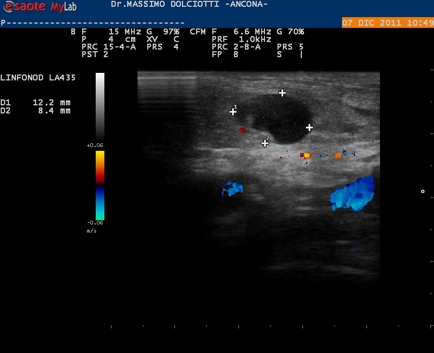

Data inserimento: 12/12/2011

Ecografia del: 07/12/2011

Strumento: Esaote MyLab 50 Gold - Responsabile Linea Cardio Esaote Regione Marche Dr. Franco Fabi

Sonda: Lineare Multifrequenza 12-18 MHz

Età Paziente: M 85 anni

Motivazione dell'esame: tumefazione inguinale, scarsamente dolente, insorta da due mesi.

Commento all'esame: le immagini ed il video documentano metastasi inguinali ipervascolarizzate in soggetto con pregressa cistectomia eseguita cinque anni fa

Conclusioni: metastasi inguinali ipervascolarizzate.